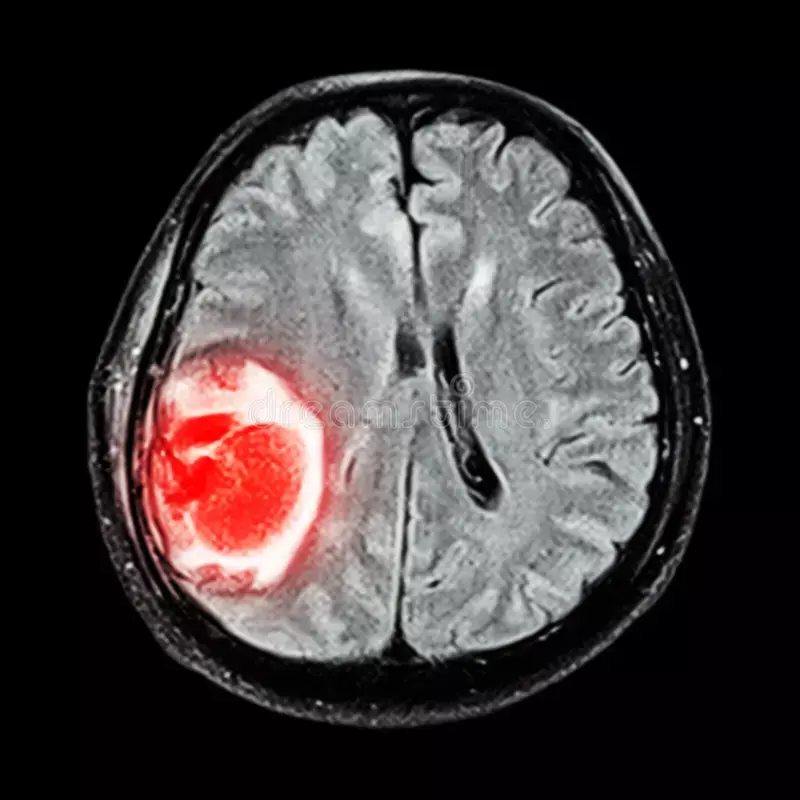

Glioblastoma: Challenges in Treatment

Glioblastoma is a very aggressive brain tumor. It’s hard to treat, and the outlook is not good. Despite trying hard, only a 5% of glioblastoma patients live ten years.

The tumor grows fast and doesn’t respond well to treatment. This makes it hard to cure.